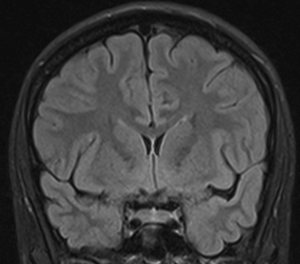

[[Fil:AntCorSylvii.png| | [[Fil:AntCorSylvii.png|300px|thumb|right|Fig.5 Et coronalt MR snit gennem den anteriore del af fissura Sylvii hvor temporallappens øvre flade er konkav]] | ||

Den superiore flade af temporallappen grænser op mod Insula inferiore halvdel. Den forreste del af denne flade er konkav (planum polare) og matcher den anteriore inferiore konvekse form af Insula, mens den posteriore supriore flade en med plan (planum temporale). Denne forskel kan tydligt erkendes på coronale MR-skanningssnit (Fig. 5+6). Overgangen mellem den konkave og den plane den af temporallappens superiore flade markere lokalisationen af Heschel's gyrus. Heschel's gyrus har et skråt forløb fra antero-lateralt til postero-medialt. Lateralt findes Heschel's gyrus lige overfor gyrus postcentral i parietallappen adskilt af lateralfissuren. Følges Heschel's gyrus medialt posteriort peger den mod atrium af ventrikelsystem lige posteriort for thalamus (Fig. 4).